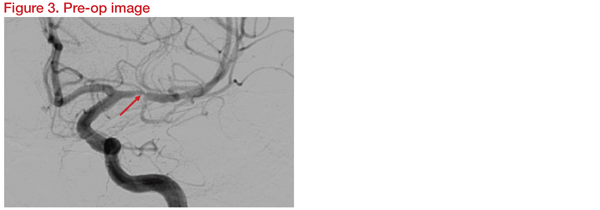

A 53-year-old man experienced recurrent episodes of right-sided weakness lasting for 5 minutes each time. The patient has hypertension (BP 190/108 mm Hg) and hypercholesterolaemia (total lipoprotein 6.7mmol/L, LDL 4.1mmol/L) and was on multiple antihypertensive medication, anticholesterol drug, and double antiplatelet therapy.

Digital subtraction angiography (DSA) revealed 85 percent short segment stenosis at left MCA, M1 just proximal to the origin of a temporal branch (Figure 3). The risk of occlusion of the origin of the temporal branch due to plaque displacement as a result of angioplasty was considered.

Three-Dimensional Rotational Angiography (3DRA) was carried out for assessment in detail and planning. Instruments planned for the procedure were the Gateway balloon 1.5*15mm and Wingspan stent 2.5*9mm. Following the intervention, DSA and 3DRA showed preservation of the temporal branch origin (Figure 4).

At 12 months, there was no evidence of branch thrombosis or in-stent restenosis. The patient was well and symptom free. This showed that angioplasty and stenting using Gateway and Wingspan is safe for M1 ICAD stenosis close to a temporal branch origin without delayed branch thrombosis or in-stent restenosis.